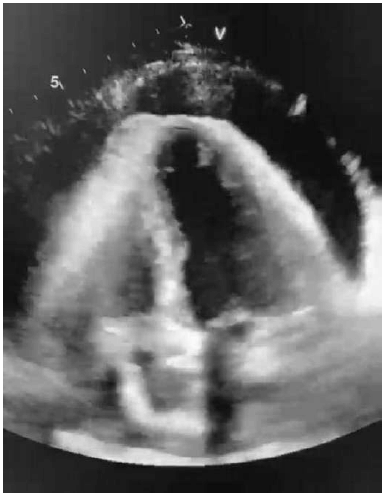

Uma paciente de 40 anos de idade chega ao pronto-socorro referindo ortopedia, edema de membros inferiores e dispneia aos pequenos esforços de início há cerca de 1 semana. Ao exame físico, apresenta-se dispneica, com extremidades frias, com palidez cutânea e com frequência cardíaca de 120 bpm; eletrocardiograma com padrão de baixa voltagem e alternância elétrica. Foi realizado ecocardiograma à beira-leito, conforme se vê na imagem abaixo.

Assinale a alternativa que indica a conduta mais adequada diante desse caso clínico.

Acerca dessa situação hipotética, assinale a alternativa que apresenta os achados clínicos mais esperados para o caso da paciente.